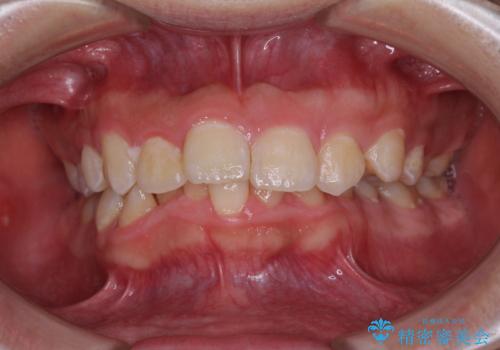

- 前歯のデコボコと右上の八重歯を気にして来院された患者様です。

マウスピース矯正とワイヤー矯正で悩んでいらっしゃいましたが、非常に強い咬合力であることや、お仕事柄不規則な生活リズムになることが多いとのことで、ワイヤー装置にて矯正治療を行うこととしました。

口元が突出する仕上がりとならないように、舌突出癖改善のトレーニングをしっかりと行っていただきながら、矯正治療を進めていくこととしました。

1年強でワイヤー装置を外すことができ、思ったよりも短期間で終了したため、患者様には大変喜んでいただきました。